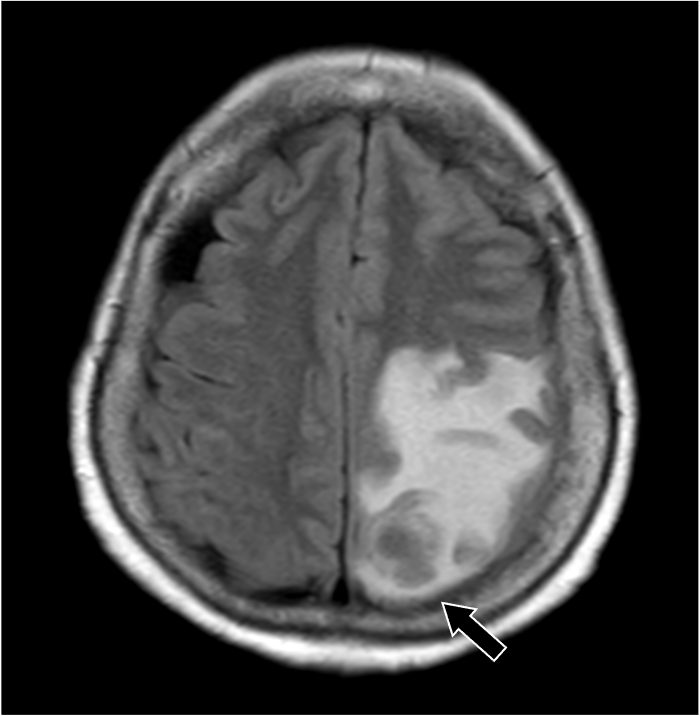

転移性脳腫瘍における造影T1強調画像の症例

202X年より右手指知覚障害、頭痛を自覚。数日後から頻回嘔吐や右下肢運動障害があり、頭部造影MRIにて精査。既往に転移性肺腫瘤の治療歴あり。

201X年腎細胞癌に対して手術を施行。術後経過で肺転移が出現。外科的切除および化学療法にて縮小を維持していた。202X年神経症状が出現し、頭部造影MRIにて左頭頂葉の孤発性脳転移と診断された。開頭腫瘍摘出術および定位照射を行い、再発なく経過している。

造影MRI検査は単純MRI検査と比較して、追加病変の検出能や診断精度の向上が示されている。造影MRI検査は、非腫瘍性白質疾患(慢性微小血管虚血性疾患など)を転移性腫瘍と鑑別する上でも有用である。脳腫瘍では腫瘍周囲に血管原性浮腫を認める場合があるが、高悪性度の原発性脳腫瘍と比較して、転移性脳腫瘍では腫瘍径に対する血管原性浮腫の面積が広いことが報告されている。単純MRI検査では腫瘍径を過大評価する可能性があり、術前・放射線治療計画等に際して造影MRI検査による適切な評価が求められる。